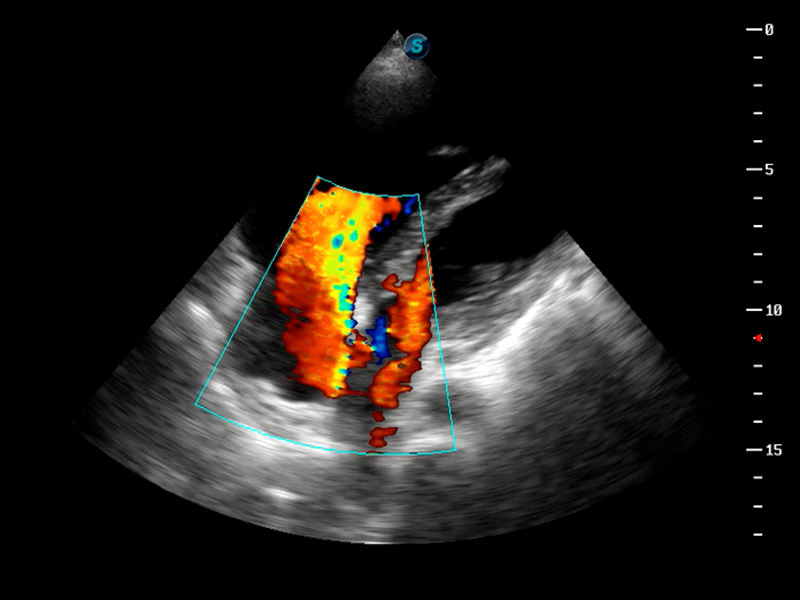

AutoC智能血流追踪